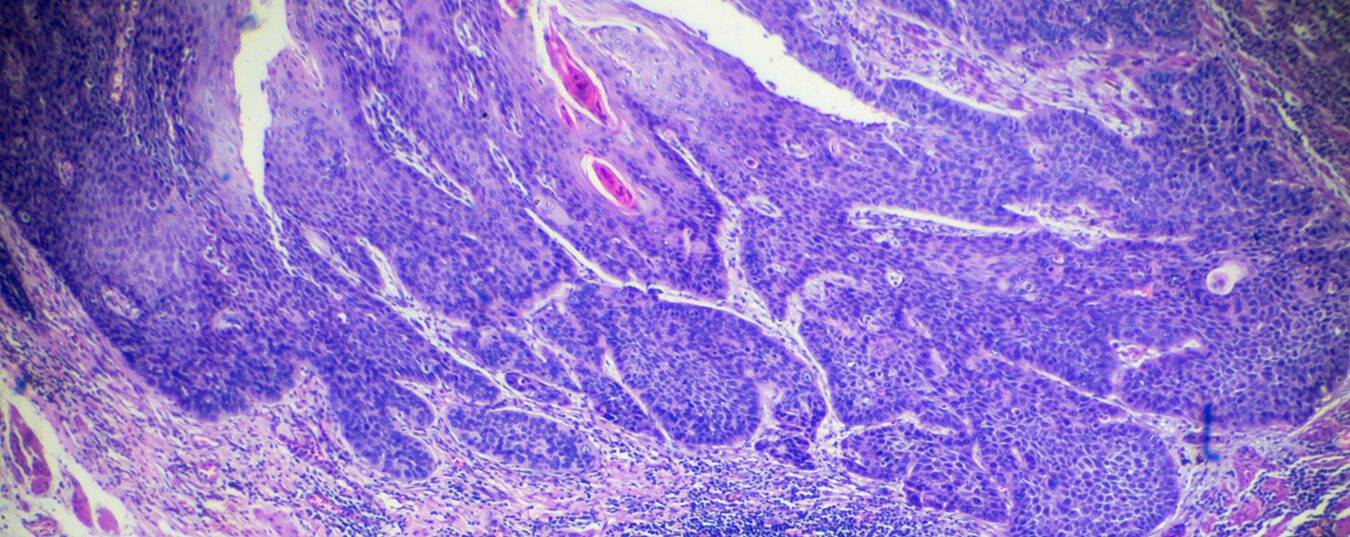

Ösophaguskarzinome sind vergleichsweise seltene Tumore und machen circa 1% aller Malignome weltweit aus. Basierend auf ihrer Lokalisation unterscheidet man zervikale und intrathorakale Tumore. Histologisch manifestieren sie sich als Plattenepithelkarzinome und Adenokarzinome. Je nach Tumor greifen andere Therapiestandards.